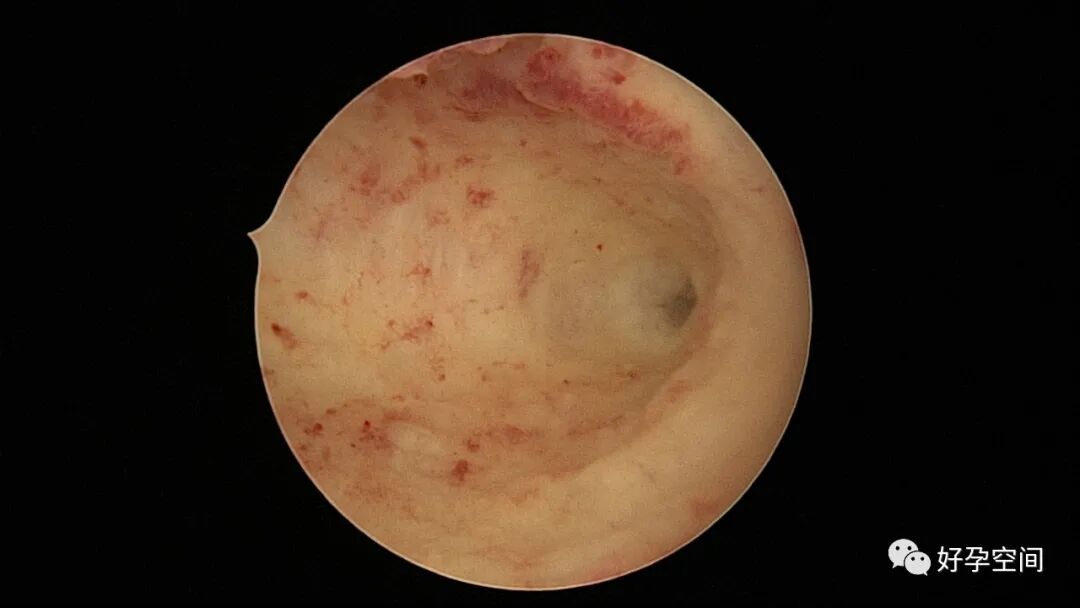

病例2:患者31岁,原发不孕,2019年11月在重庆某妇幼保健院做宫腹腔镜手术疏通输卵管,术中未取内膜活检,术后未孕。2021年7月在成都某大型生殖中心试管怀孕双胎(移植前未做宫腔镜检查及内膜活检),2021年11月孕4月双胎破水,在达州当地医院引产清宫,清宫术后40天复诊B超提示宫腔胚物残留。2022年1月到我院(眉山蕴缨妇产医院)行宫腔镜手术切除残留组织,2022年4月宫腔镜术后3个月复诊B超提示宫腔粘连,再次来我院行宫腔镜分粘。宫腔被覆一层沙丘状质脆增生组织,宫腔下段两侧壁内聚,行分粘术,取内膜送病检。

子宫内膜结核是由结核分枝杆菌在子宫内膜部位种植引起的炎症,是仅次于输卵管结核的常见女性生殖器结核。子宫内膜结核常由输卵管结核蔓延而来,多继发于盆腔腹膜结核或肺结核。子宫内膜结核的超声表现主要为:子宫内膜回声不均匀、宫腔内结节样病灶、宫腔内强回声灶、单纯的子宫内膜薄等。盆腹腔超声显示输卵管炎性表现:输卵管增粗、肥厚、扭曲、僵硬、输卵管积液积脓、卵巢旁混合性包块、输卵管系膜囊肿、盆腔包裹性积液等。术中所见:盆腹腔组织粘连、盆腹腔粟粒样结节、结核球、脓肿等,输卵管伞端烟斗样外翻,输卵管内充满淡黄色干酪样或豆渣样组织。宫腔镜显示宫腔狭窄、宫壁僵硬、宫内膜肉芽肿样增生、内膜质脆易刮除、干酪样组织、脓液等。

温宝宁等将子宫内膜结核宫腔镜检查的镜下表现分为:①宫腔形态、大小正常,双侧输卵管开口可见,子宫内膜发红、增厚,局部突起,表面可见少量质脆的小颗粒状赘生物,可刮出质脆的子宫内膜组织;②宫腔形态正常,但是宫腔内无正常子宫内膜,均被覆一层苍白的绒毛状或棉絮状质脆组织,血管少,无异形血管,宫腔内病灶与正常组织分界明显;③宫腔形态异常,呈窄桶状,子宫内膜瘢痕化,输卵管开口细小,甚至宫角消失。